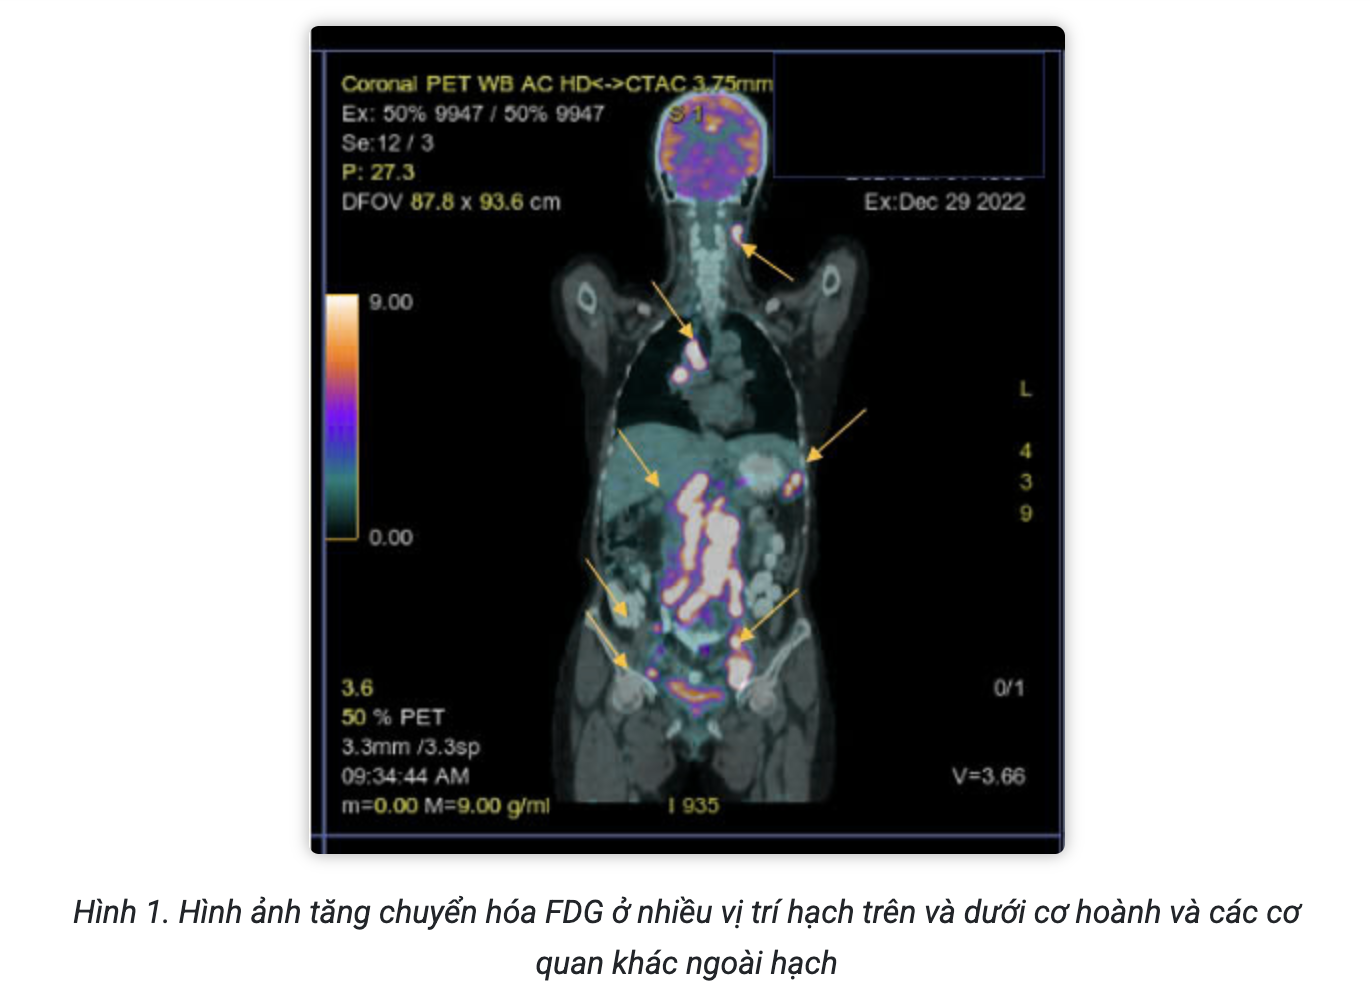

Dày vách thực quản đoạn tâm vị 15mm, chùm hạch lớn 5cm vùng cạnh đầu và thân tụy.

Hạch dạng di căn 12mm vùng thượng đòn trái.

Dầy thành thực quản 15mm kéo dài 1/3 cuối thực quản, bắt thuốc cản quang mạnh, chùm hạch lớn vùng đầu tụy 5cm

Hạch 14mm vùng thượng đòn trái

Chẩn đoán: k thực quản đoạn 1/3 dưới di căn hạch thượng vị và thượng đòn trái.